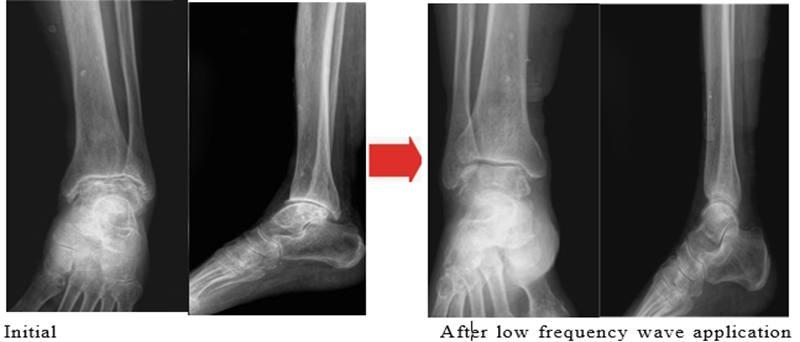

To provide preliminary clinical context for the proposed physical mechanisms, we describe an exploratory single-patient observation in which low-frequency field exposure was associated with symptomatic and structural improvement in end stage ankle osteoarthritis. This case is presented for hypothesis-generating purposes only. An 84-year-old female patient had a complex medical history including right pontine infarction (2021), atrial fibrillation, and a recent episode of acute pyelonephritis. She also suffered from left ankle end-stage osteoarthritis with associated avascular necrosis, resulting in chronic pain, limited mobility, and functional impairment. Laboratory findings at the time of evaluation showed evidence of systemic inflammation and medical comorbidity, including white blood cell count of 14,000/μL, erythrocyte sedimentation rate (ESR) of 33 mm/hr, and blood urea nitrogen/creatinine of 22.4/1.19 mg/dL. Given her advanced age, neurological history, infection risk, and cardiovascular comorbidities, surgical intervention was considered high risk. A noninvasive low frequency electromagnetic wave intervention was therefore applied locally to the affected ankle joint. The treatment was administered for 4 consecutive weeks, at a duration of 1 hour per day, under close clinical monitoring. Following the treatment period, the patient demonstrated clinically meaningful improvement in ankle pain and joint function, accompanied by improved weight bearing tolerance. Radiographic and/or imaging-based assessment showed partial improvement in joint space narrowing, consistent with enhanced synovial lubrication rather than structural cartilage regeneration (Figure 1). No acute adverse events, arrhythmia exacerbation, or infectious complications were observed during the intervention period. From a mechanistic standpoint, these observations are consistent with the physical framework proposed in this study. Low-frequency electromagnetic fields are expected to influence hydration-mediated boundary lubrication, polymer conformation, ionic distribution, and interfacial fluid dynamics within synovial environments, rather than acting through phonon excitation or quantum vibrational modes. In the presence of graphene–DNA–like hydrated interfaces (either endogenous or exogenously introduced), such field modulation could plausibly enhance synovial fluid lubrication efficiency, reduce interfacial friction, and attenuate mechanically driven inflammation. It is emphasized that this single case does not establish causality, nor does it demonstrate cartilage regeneration or disease reversal. Instead, it supports the biophysical plausibility that low frequency field modulation of hydrated joint interfaces may yield functional benefits even in advanced degenerative disease. Controlled clinical trials and well defined material delivery studies are required to determine efficacy, dose– response relationships, durability, and safety.

Figure 1. Following the treatment period, the patient demonstrated clinically meaningful improvement in ankle pain and joint function, accompanied by improved weight bearing tolerance. Radiographic and/or imaging-based assessment showed partial improvement in joint space narrowing, consistent with enhanced synovial lubrication rather than structural cartilage regeneration.